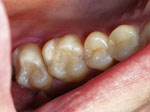

In the images above, the back 2 teeth used to be filled with dark silver fillings and they were replaced with beautiful bonded restorations.